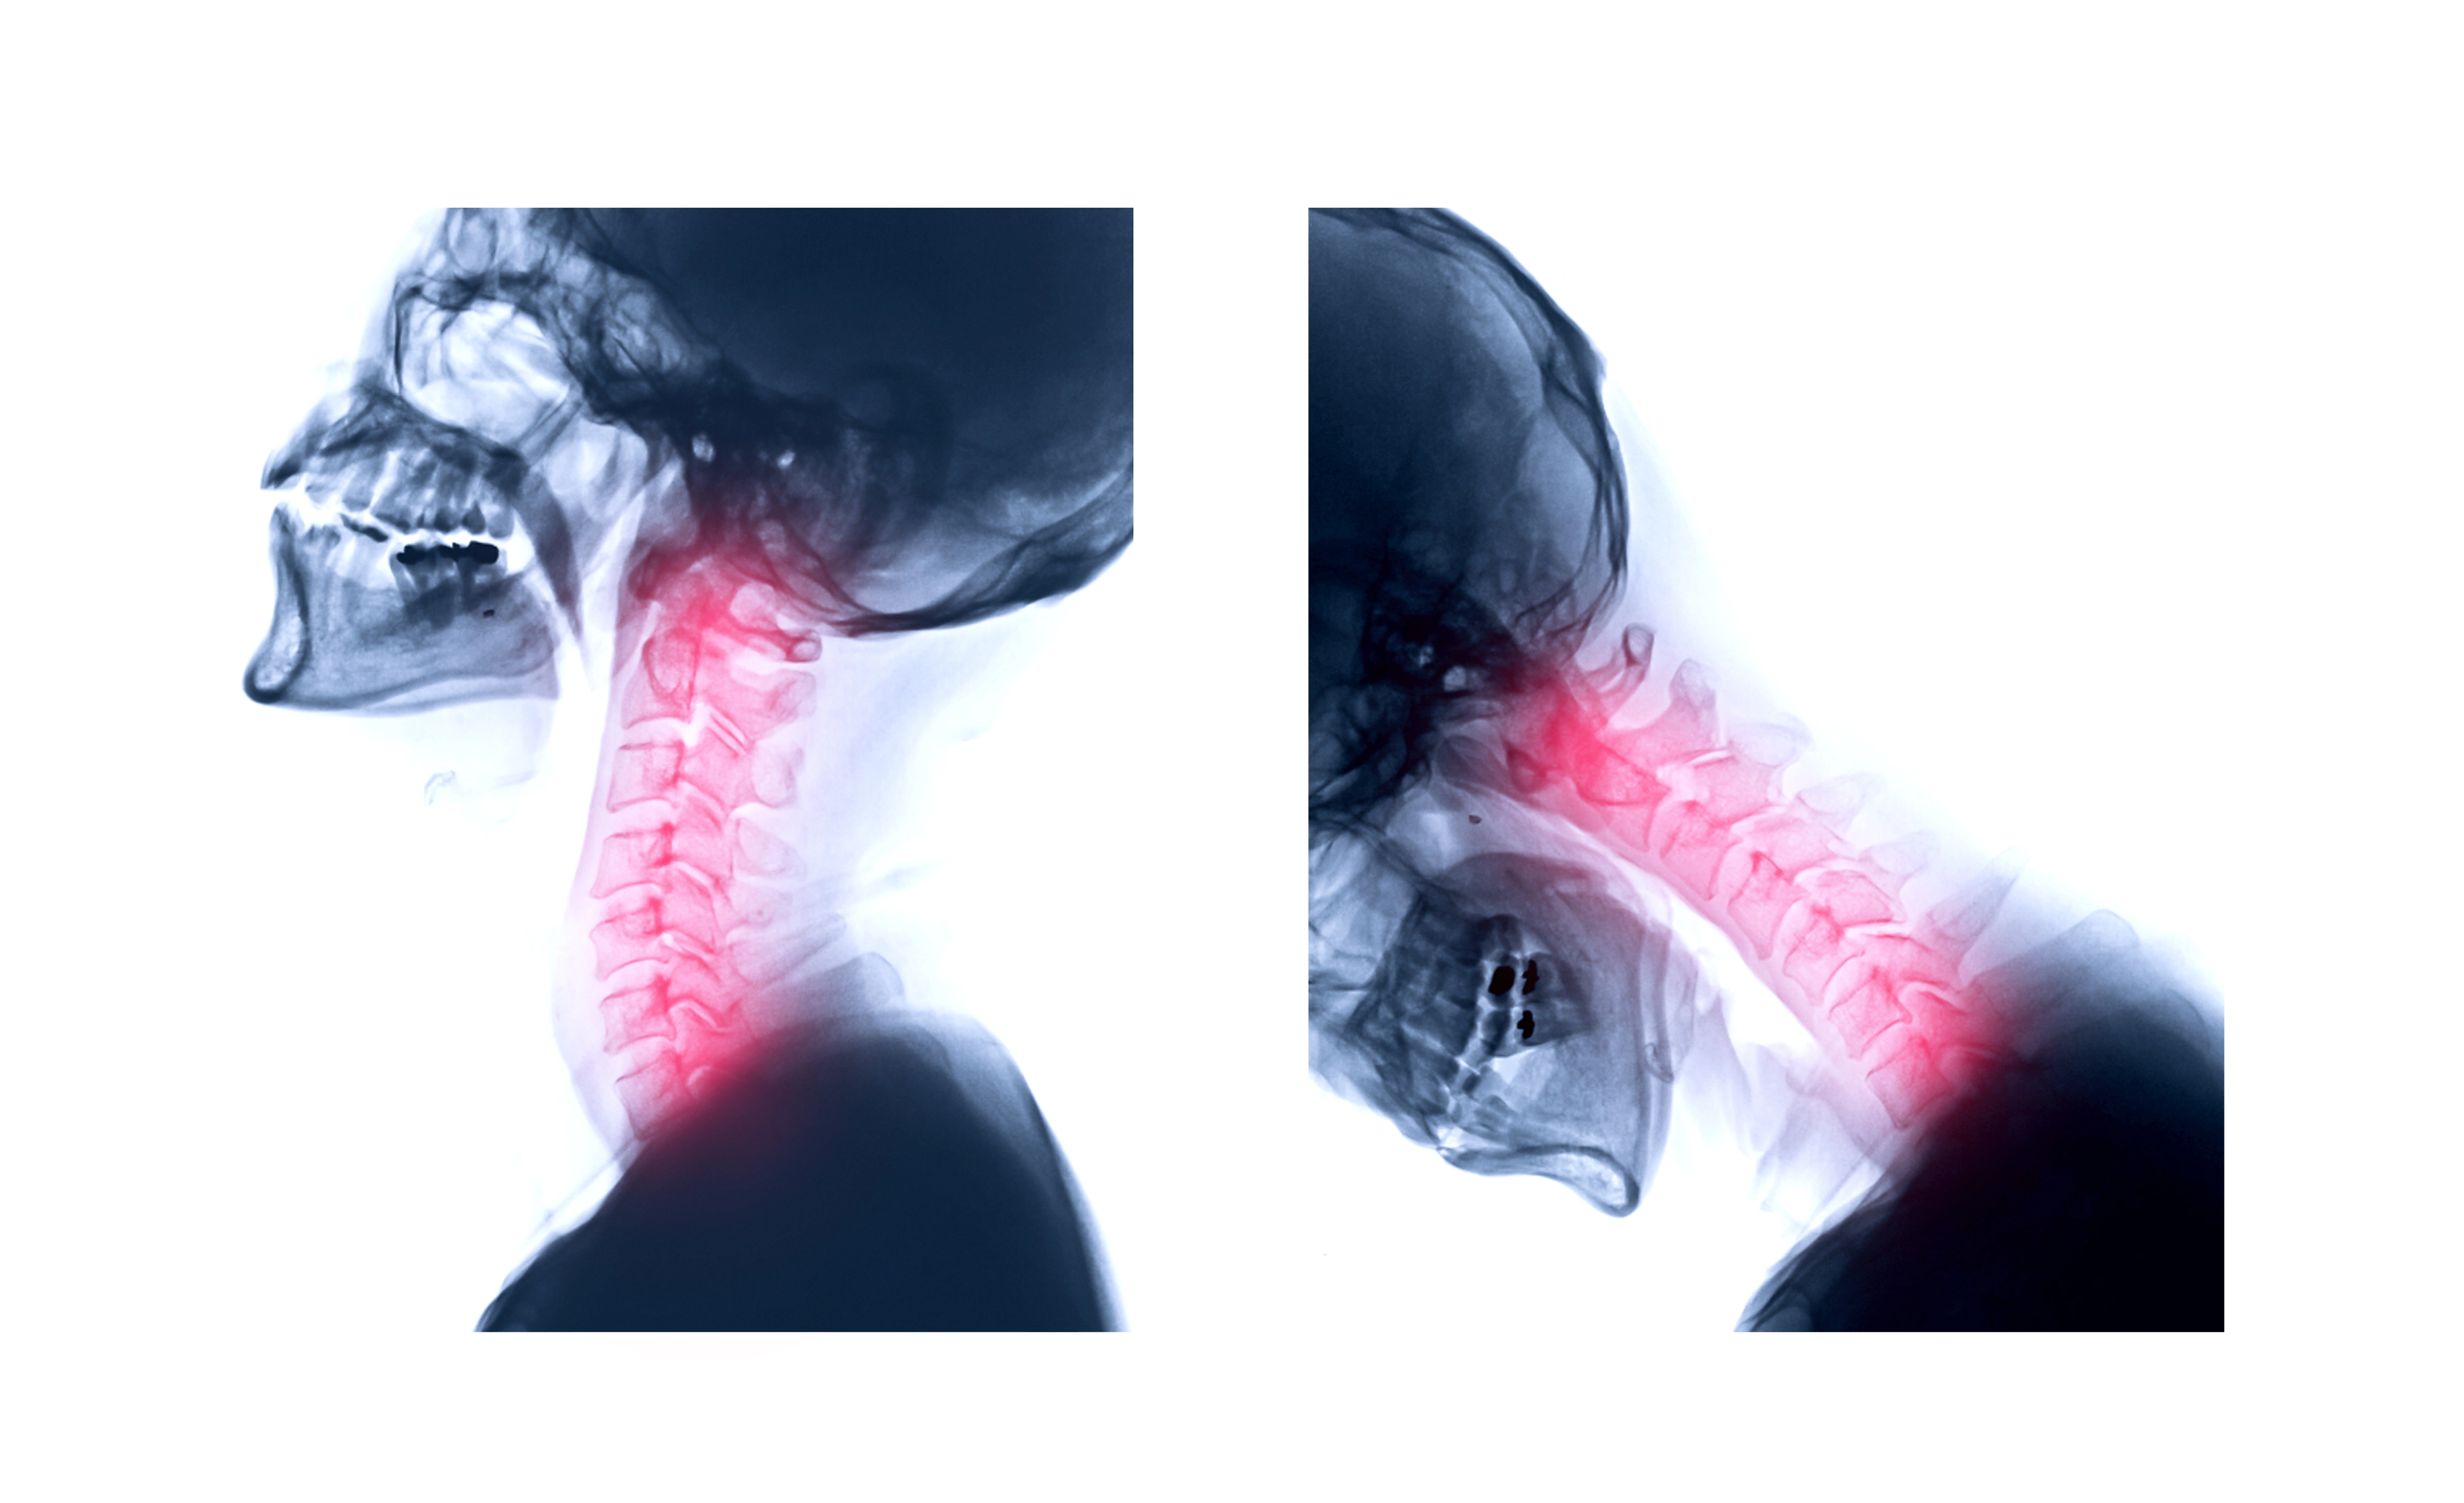

목 디스크는 목 부분의 척추와 척추 사이에 위치한 디스크가 눌리거나 훼손되는 상태를 말합니다. 이 글에서는 '목 디스크 터지면' 어떤 증상이 나타나는지, 그 원인은 무엇인지에 대해 알아보겠습니다.

디스크는 척추 뼈 사이에 있는 쿠션 같은 구조로, 척추 뼈를 보호하고 충격을 흡수하는 역할을 합니다. '목 디스크가 터진다'는 표현은 디스크의 내부에 있는 젤리 같은 물질이 바깥으로 나오는 상태를 의미합니다.